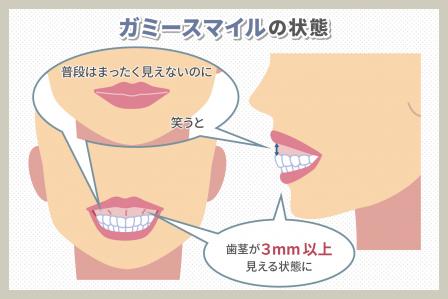

外科矯正手術(セットバック手術など)はどんな場合に適している?

セットバック手術(前方分節骨切り術)は、骨格が原因で起こる重度の出っ歯や受け口、口ゴボなどを根本的に改善するために行われる外科的な矯正方法です。歯列矯正だけでは十分に後退しきれない顎の突出を、直接骨を切り、適切な位置に移動させることで治療します。フェイスラインを整えられることから美容整形的な要素も含まれますが、その一方でリスクやダウンタイムがあるため、慎重に検討が必要です。

最近では、症状の程度や医療機関の設備・方針によっては日帰り手術で対応できるケースも見られます。術後の経過観察や痛み止めの処方をしっかり行えば、長期入院をしなくても日常生活に早期復帰できることがあります。ただし、術後は腫れや痛みが出やすいこと、一定期間は食事や顎の動きに注意が必要なことは変わらないため、術後ケアや通院スケジュールをあらかじめ確認しておきましょう。

セットバック手術は、顎の骨を切り移動させるリスク、術後の腫れや痛み、数日から数週間にわたるダウンタイムなどが伴います。

たとえ日帰りで行える場合でも、個人の症状や病院の方針によっては入院が必要となるケースもあるため、専門医との綿密な治療計画が欠かせません。

大きな見た目の改善効果が得られる反面、術後ケアや生活面の調整が必要になる点も踏まえ、十分に検討した上で治療を選択しましょう。